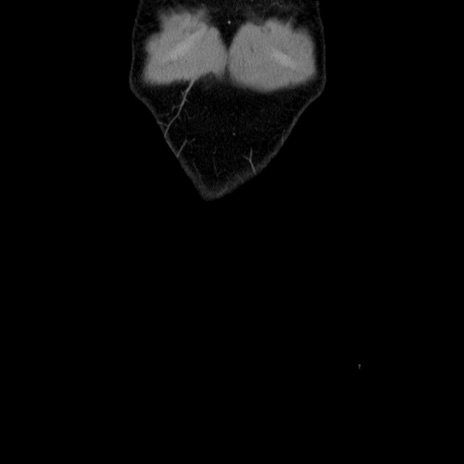

症例36(冠状断像)

【症例】20歳代 男性

【主訴】心窩部痛

【現病歴】今朝より上腹部痛あり。一旦軽快していたが再度出現したため救急要請。昨日夕に白身の魚を含む刺身を食べた。

【身体所見】BP 136/89mmHg、HR 74/min、BT 37.0℃、腹部:膨満、軟、心窩部に圧痛あり。反跳痛なし、筋性防御なし、腸雑音やや亢進あり。

【データ】WBC 17700、CRP 0.48